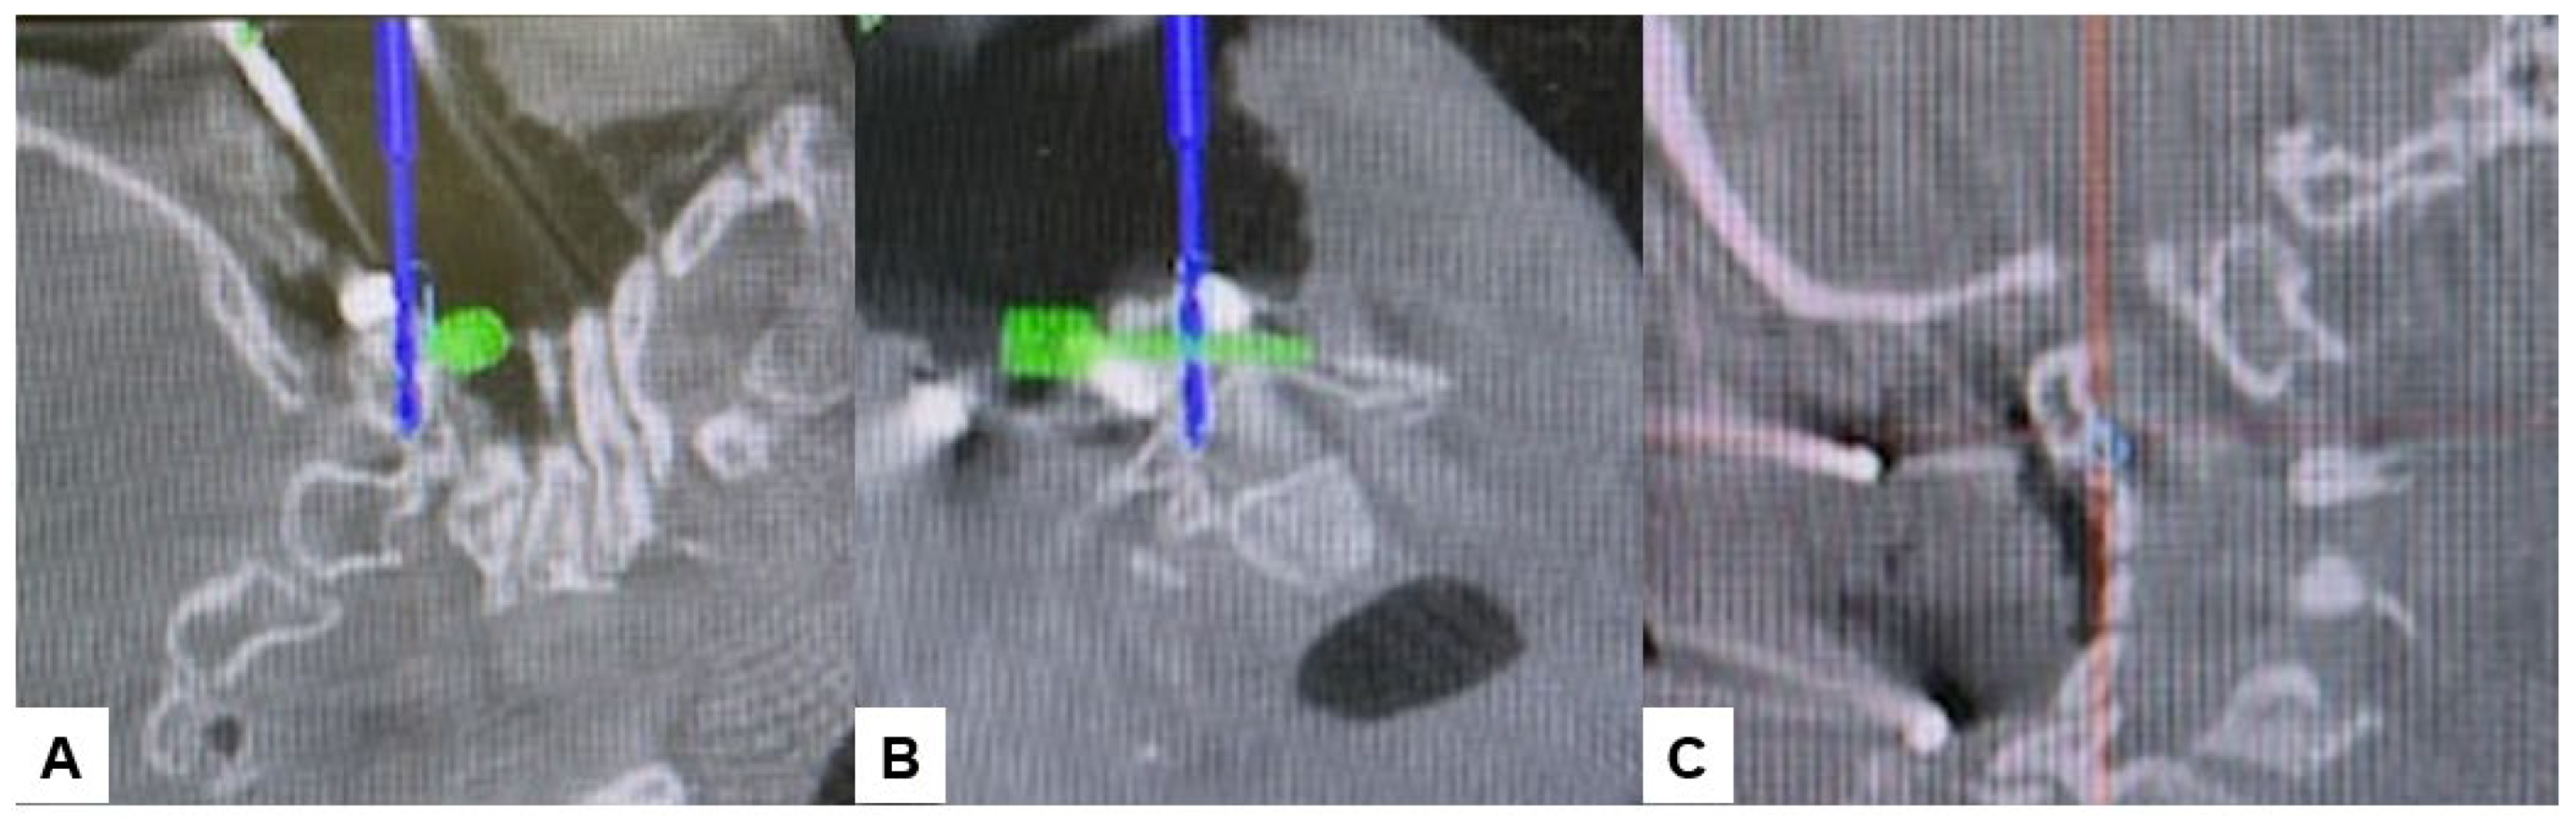

2.4. Surgery